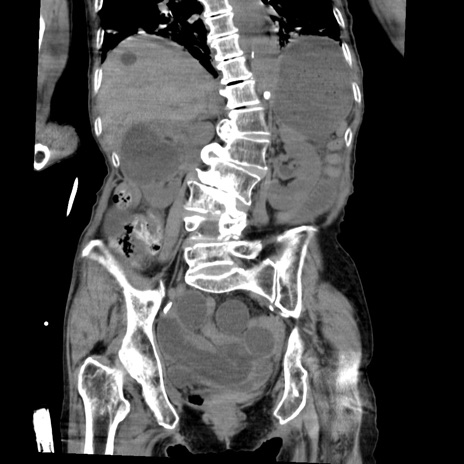

症例27(冠状断像)

【症例】80歳代女性

【主訴】嘔吐、腹痛

【現病歴】数時間前より嘔吐あり。心窩部痛出現し、徐々に右下腹痛あり。その後も数回嘔吐あり救急搬送となる。

【既往歴】左大腿骨頚部骨折手術

【身体所見】腹部は膨隆しているが軟らかく圧痛なし。腸雑音はやや亢進。

【データ】WBC 12000、CRP 19.05